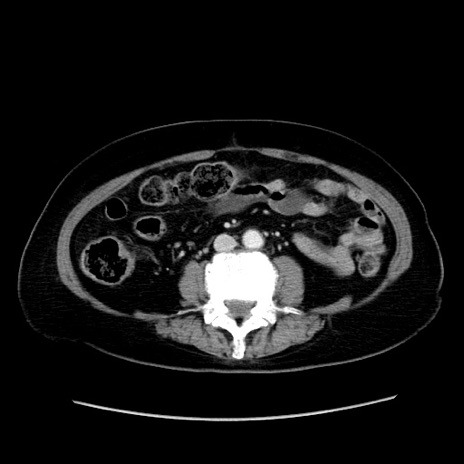

症例19(横断像)

【症例】80歳代女性

【主訴】下腹部痛

【現病歴】約8時間前より下腹部痛の出現あり、救急外来受診。

【既往歴】両側付属器切除

【身体所見】意識清明、下腹部正中に手術痕あり、その部位に一致して圧痛と反跳痛あり。腸蠕動音は亢進。

【データ】WBC 9300、CRP 0.15